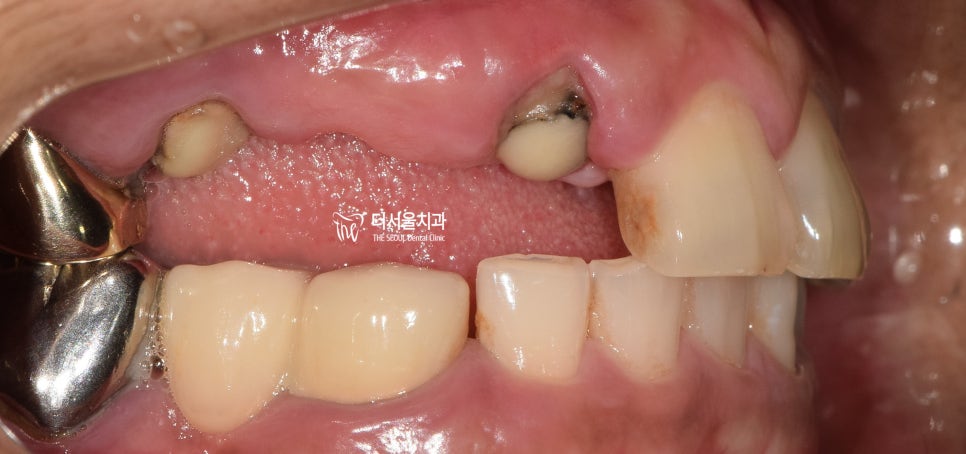

힘겨운 발치가 끝이 났네요.

주변 조직에 영향을 끼치지 않고

안전하게 제거해 드렸습니다.

이제 픽스처를 심어야겠죠?